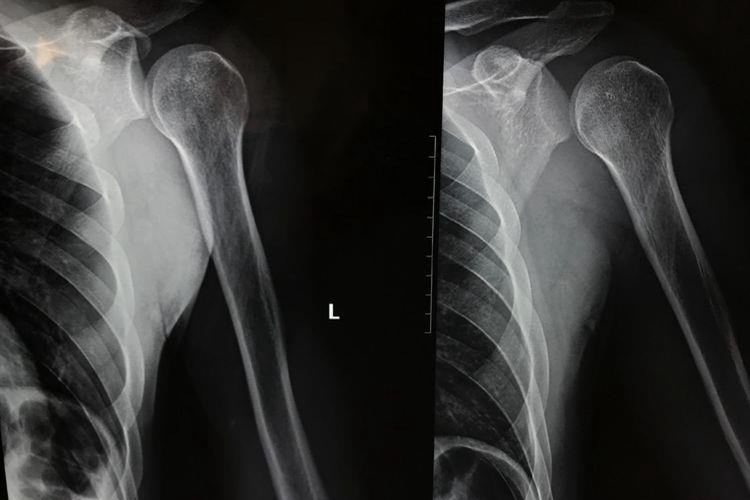

肩关节脱位主要由于暴力导致,可出现肩部疼痛、肿胀、活动障碍等症状,借助X线可了解肱骨头脱位类型,一般分为前脱位和后脱位。

肩关节脱位患者常有上肢外展外旋或后伸着地受伤史,可出现肩部疼痛、肿胀、活动障碍,以及有以健手托住病侧前臂、头向病侧倾斜的特殊姿势。通常X线检查可确诊,常见肱骨头前脱位,偶见肱骨头后脱位。肱骨头前脱位可见X线片骨影向下移位,位于肩胛盂下方,称为盂下脱位,此外还可向上移位,位于喙突下方或锁骨下方等位置。肱骨头后脱位一般表现为肱骨头在肩胛盂后方。